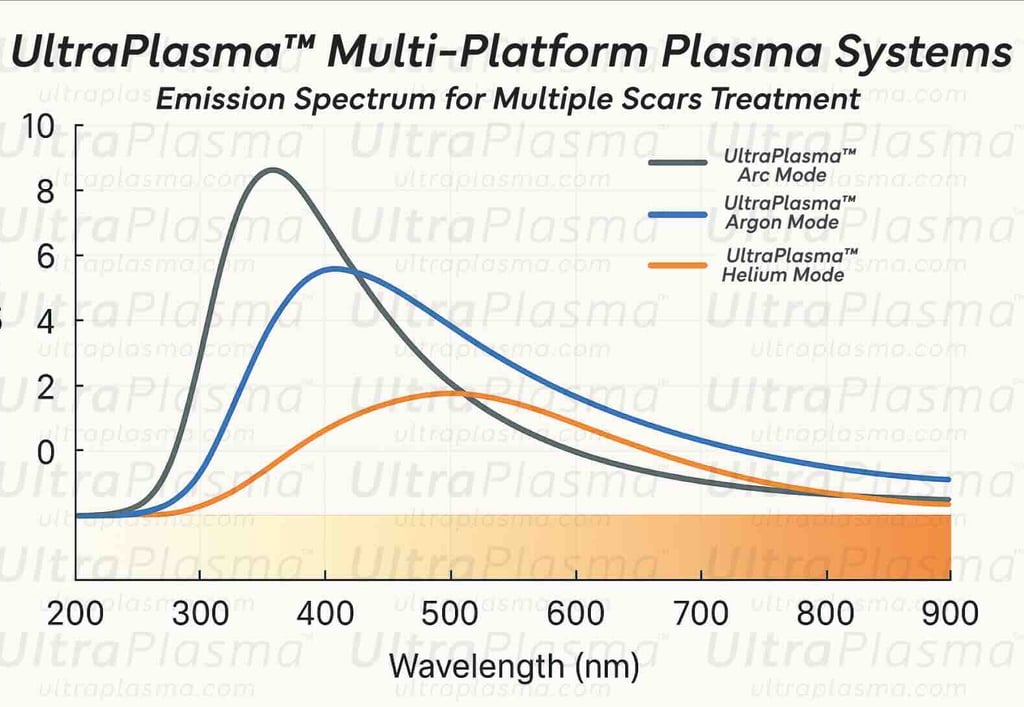

Advanced Scar Treatment Using UltraPlasma™ Multi-Platform Plasma Systems

Scarring, a complex biological response to dermal injury, manifests in various forms including surgical, hypertrophic, keloid, atrophic, stretch marks (striae), and umbilical scars. Traditional treatments often fall short due to the variability in scar biology and patient response. UltraPlasma™, a next-generation dermatological technology integrating arc, argon, and helium plasma modalities, offers a multi-depth, multi-function strategy. This article explores the anatomical, biological, and engineering principles behind scar remediation using UltraPlasma™, including the effects on skin layers, reactive species interactions, and clinical applications.

Scar formation is a natural consequence of dermal injury, often resulting in cosmetic and functional challenges depending on severity, location, and healing dynamics. Modern regenerative dermatology seeks to modulate scar tissue and restore healthy skin architecture through advanced technologies. UltraPlasma™ represents a novel multi-platform plasma treatment that combines arc, argon, and helium plasma modalities for controlled tissue interaction. This article details the mechanisms, anatomical penetration, and physicochemical gas interactions—including ozone (O₃), nitric oxide (NO), and reactive oxygen/nitrogen species (RONS)—targeted at epidermal, dermal, and hypodermal layers. Clinical and histological outcomes in treating atrophic, hypertrophic, and keloid scars on the face and body are discussed.

Scars arise from a disrupted wound healing process characterized by collagen overproduction or tissue loss. Depending on the scar type, tissue architecture, fibroblast activity, and vascularization vary significantly. UltraPlasma™ utilizes tunable plasma emissions to precisely target scarred skin layers and restore healthy tissue dynamics through oxidative, thermal, and biochemical pathways.

3.2 Plasma Modalities and Depth Effects

UltraPlasma™ Arc Plasma Mode (AP): Surface ablation, disinfection, pigment correction (~epidermis).

UltraPlasma™ Argon Plasma Mode (ArP): ECM remodeling, vascular modulation (~mid-dermis).

UltraPlasma™ Helium Plasma Mode (HeP): Deep fibroblast regulation, adipocyte signaling (~hypodermis).

UltraPlasma™ technology offers a differentiated therapeutic approach through customizable depth and plasma composition. Unlike ablative lasers or monotherapy devices, its triple-mode design allows precise control of oxidative stress, cellular modulation, and structural remodeling. Combined RONS dynamics yield comprehensive antifibrotic, vasoregulatory, and regenerative benefits.

The UltraPlasma™ multi-platform system represents a paradigm shift in scar management. By leveraging the unique interactions of arc, argon, and helium plasma with skin biology and gas chemistry, it enables personalized, multi-layered treatments for a wide range of scar pathologies.